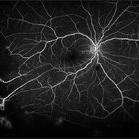

Proliferative Sickle Cell Retinopathy

Feb 1 2023 by Olivia Rainey

Ultra-widefield fluorescein angiography of a 25-year old male with Proliferative Sickle Cell Retinopathy affecting his left eye. Patient stated that he was born with Sickle disease (SC), and has yearly eye exams. He noted no vision concerns over the last year but has typically experienced sickle attacks about 1-2 per year. The physician noted that the fluorescein obtained showed peripheral nonperfusion affecting the patient's nasal and temporal retina as well as neovascularization affecting his left eye more than his right. He recommended pan retinal photocoagulation in his left eye for his temporal and nasal retina, as as well as his right eye following.

Photographer: Olivia Rainey, OCT-C, COA

Imaging device: Optos California

Condition/keywords: early phase, fluorescein angiogram (FA), fluorescein leakage, left eye, neovascularization (NV), proliferative retinopathy, sickle cell retinopathy, ultra-wide field imaging, ultra-widefield image